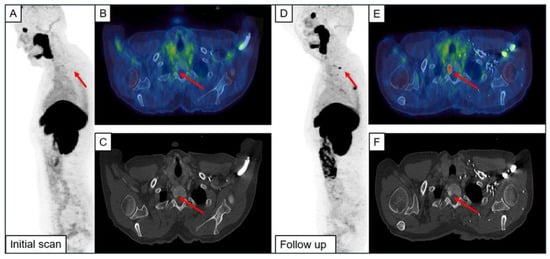

An example of a newly formed metastasis and one originating from UBU is illustrated in Figure 3.

Figure 3.

Example of a newly emerged bone metastasis (A–F) and metastases originating from focal unspecific bone uptake (G–L). The initial scan (IS) and the follow-up imaging (FU) are shown. Red arrows indicate the metastases.